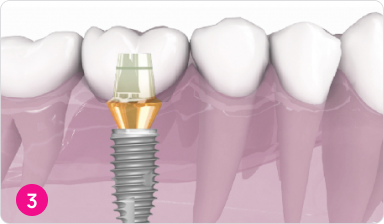

Процедура протезирования

Коронка прочно фиксируется на установленный абатмент